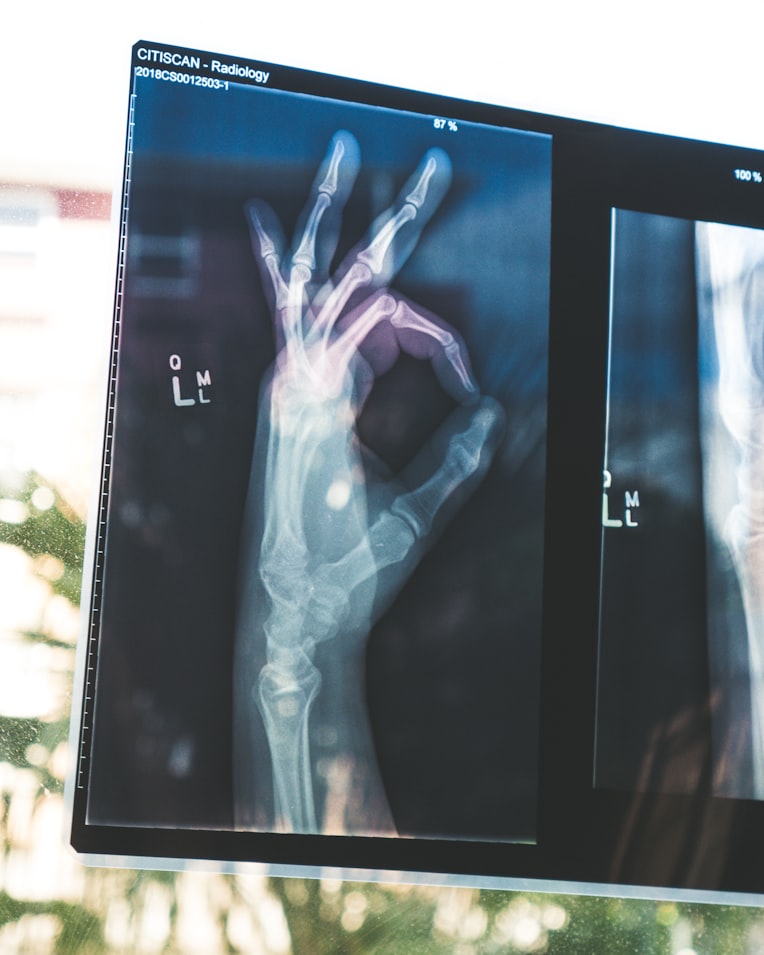

- Vitamin D deficiency is associated with an increased risk of bone fractures. This has drastic consequences for older people.

- Vitamin D, together with calcium, increases bone density.

- Vitamin D deficiency increases the risk of osteoporosis.